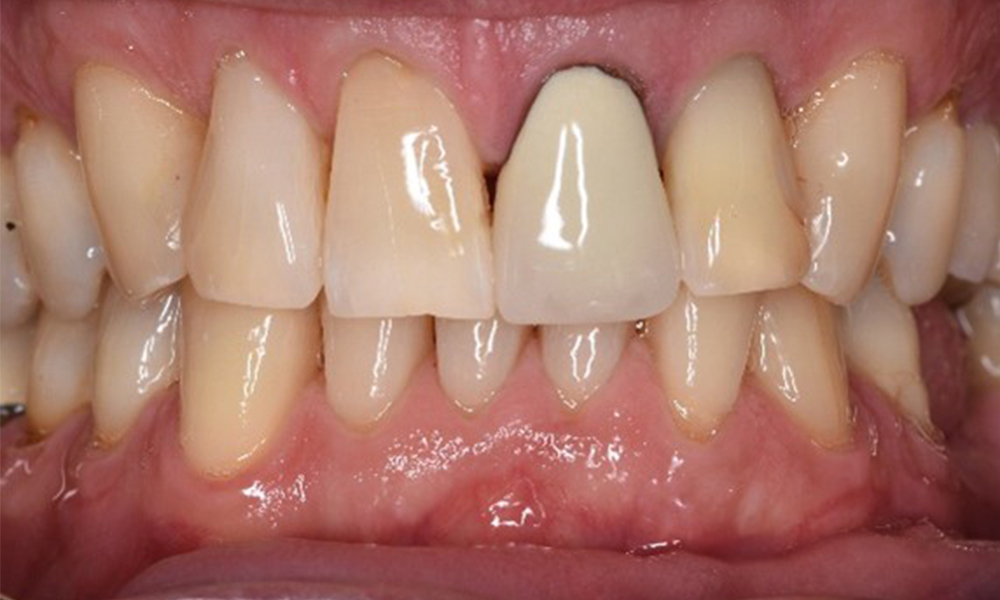

In the medical history, the 55-year-old patient states that he has no systemic disease and is not taking any medication. The patient’s lifestyle is similarly unremarkable. The patient has a few tooth restorations and two implants (2nd and 4th quadrants). On the basis of current findings, gingivitis is identified in an otherwise stable periodontal condition on the reduced periodontium (stage III, grade A).

Previous treatments: dental restorations (non-precious metal/ceramic blend), two implants (2nd, 4th quadrants)

The patient has no particular risk factors with specific dental implications. The key factor, therefore, is the requirement in terms of oral health. In this respect, good oral health is evident with stable, reduced periodontium. Should evidence of an increase in probe depth compared with the baseline, combined with diffuse bleeding, be found at a check-up appointment, diagnosis using X-ray imaging (dental X-ray) should be undertaken in order to identify peri-implant bone loss at an early stage and intervene accordingly.

On the basis of the stable periodontal and peri-implant situation, it is recommended that the patient should have check-ups every six months.